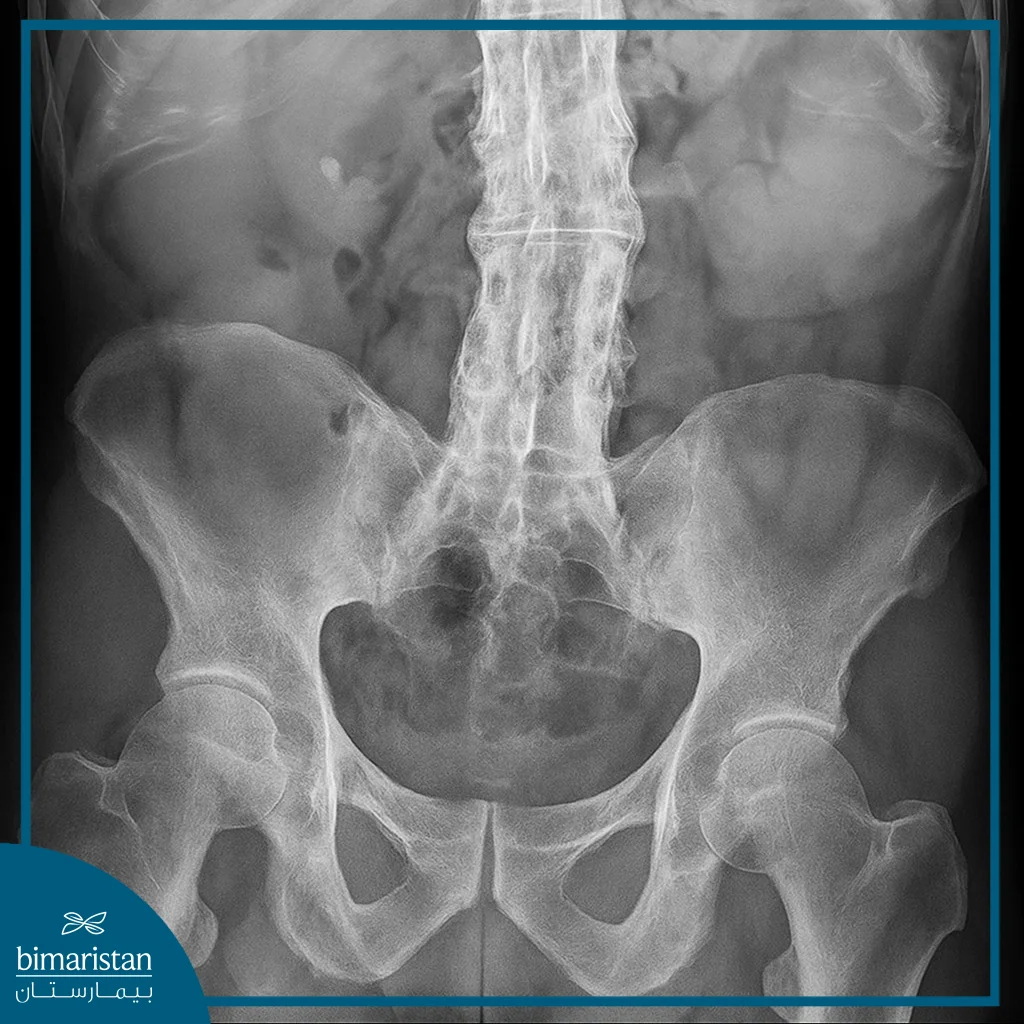

يُعتمد في تشخيص التهاب الفقرات التصلبي على مزيج من الأعراض السريرية، والفحوص المخبرية، والصور الشعاعية التي تكشف التبدلات الالتهابية والهيكلية في العمود الفقري والمفاصل العجزية الحرقفية، يهدف التشخيص المبكر إلى بدء العلاج في الوقت المناسب لتخفيف الالتهاب ومنع حدوث التيبّس الدائم في الفقرات، طرق التشخيص تشمل:

- التصوير الشعاعي: يُظهر الأشعة السينية تغيّرات المفاصل العجزية الحرقفية والعمود الفقري في المراحل المتقدمة، بينما تساعد صور الرنين المغناطيسي في اكتشاف الالتهاب في مراحله المبكرة قبل ظهور التبدلات العظمية.